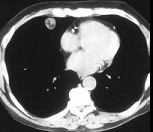

- 单项选择题女,71岁, 咳嗽,咳痰, 胸部隐痛2月余,请结合影像学检查, 选出最可能的诊断 ( )

A、肺癌

B、肺结核

C、肺错构瘤

D、结节病

E、肺转移瘤